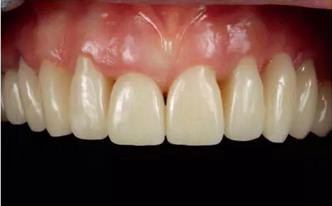

除了純的PMMA基材料(例如:Telio CAD,義獲嘉偉瓦登特,列支敦士登;artBlocTemp,Merz 公司,德國)外(圖1),還出現(xiàn)了各種材料組合。通過使用陶瓷填料,而使材料的性能得到優(yōu)化并適合于長期的臨床使用。為了對不同材料有一個正確的認識,以一個共識會議所提出的內(nèi)容為基礎(chǔ),將在下文對各類材料組合進行探討6。

圖1:單純由PMMA 切削而成的長期臨時修復(fù)體戴入口內(nèi)后的情況。